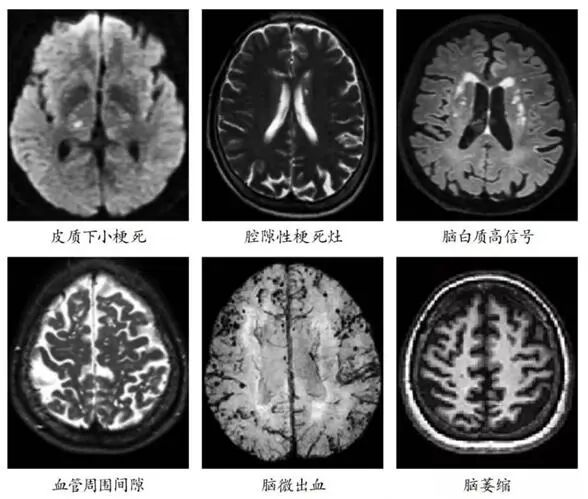

中老年人头颅磁共振(MRI)报告上经常有的腔隙性脑梗死、脑白质高信号等,并非正常衰老的表现,而是脑小血管病(CSVD)的典型信号。CSVD被称作“沉默脑杀手”,因为它早期无症状、进展缓慢,不会引起人们的重视,在不知不觉中损害了患者的运动及认知功能。

脑小血管病,指大脑内直径小于200微米的微小血管(包括小动脉、毛细血管、小静脉)发生退行性病变、堵塞或轻微渗漏,就像脑部深处的“微小水管”慢慢老化、不通畅,进而导致脑组织慢性缺血缺氧,神经功能出现渐进性损伤。

它和我们常说的急性大中风有明显区别:大中风发病急、肢体偏瘫等症状突出,容易被及时察觉;而脑小血管病起病极为隐匿,早期几乎没有特异性症状,进展缓慢,极易被当成正常衰老忽视。临床数据显示,60岁以上人群发病率超30%,90岁以上人群接近100%,也是诱发血管性痴呆、老年人反复跌倒的主要元凶。